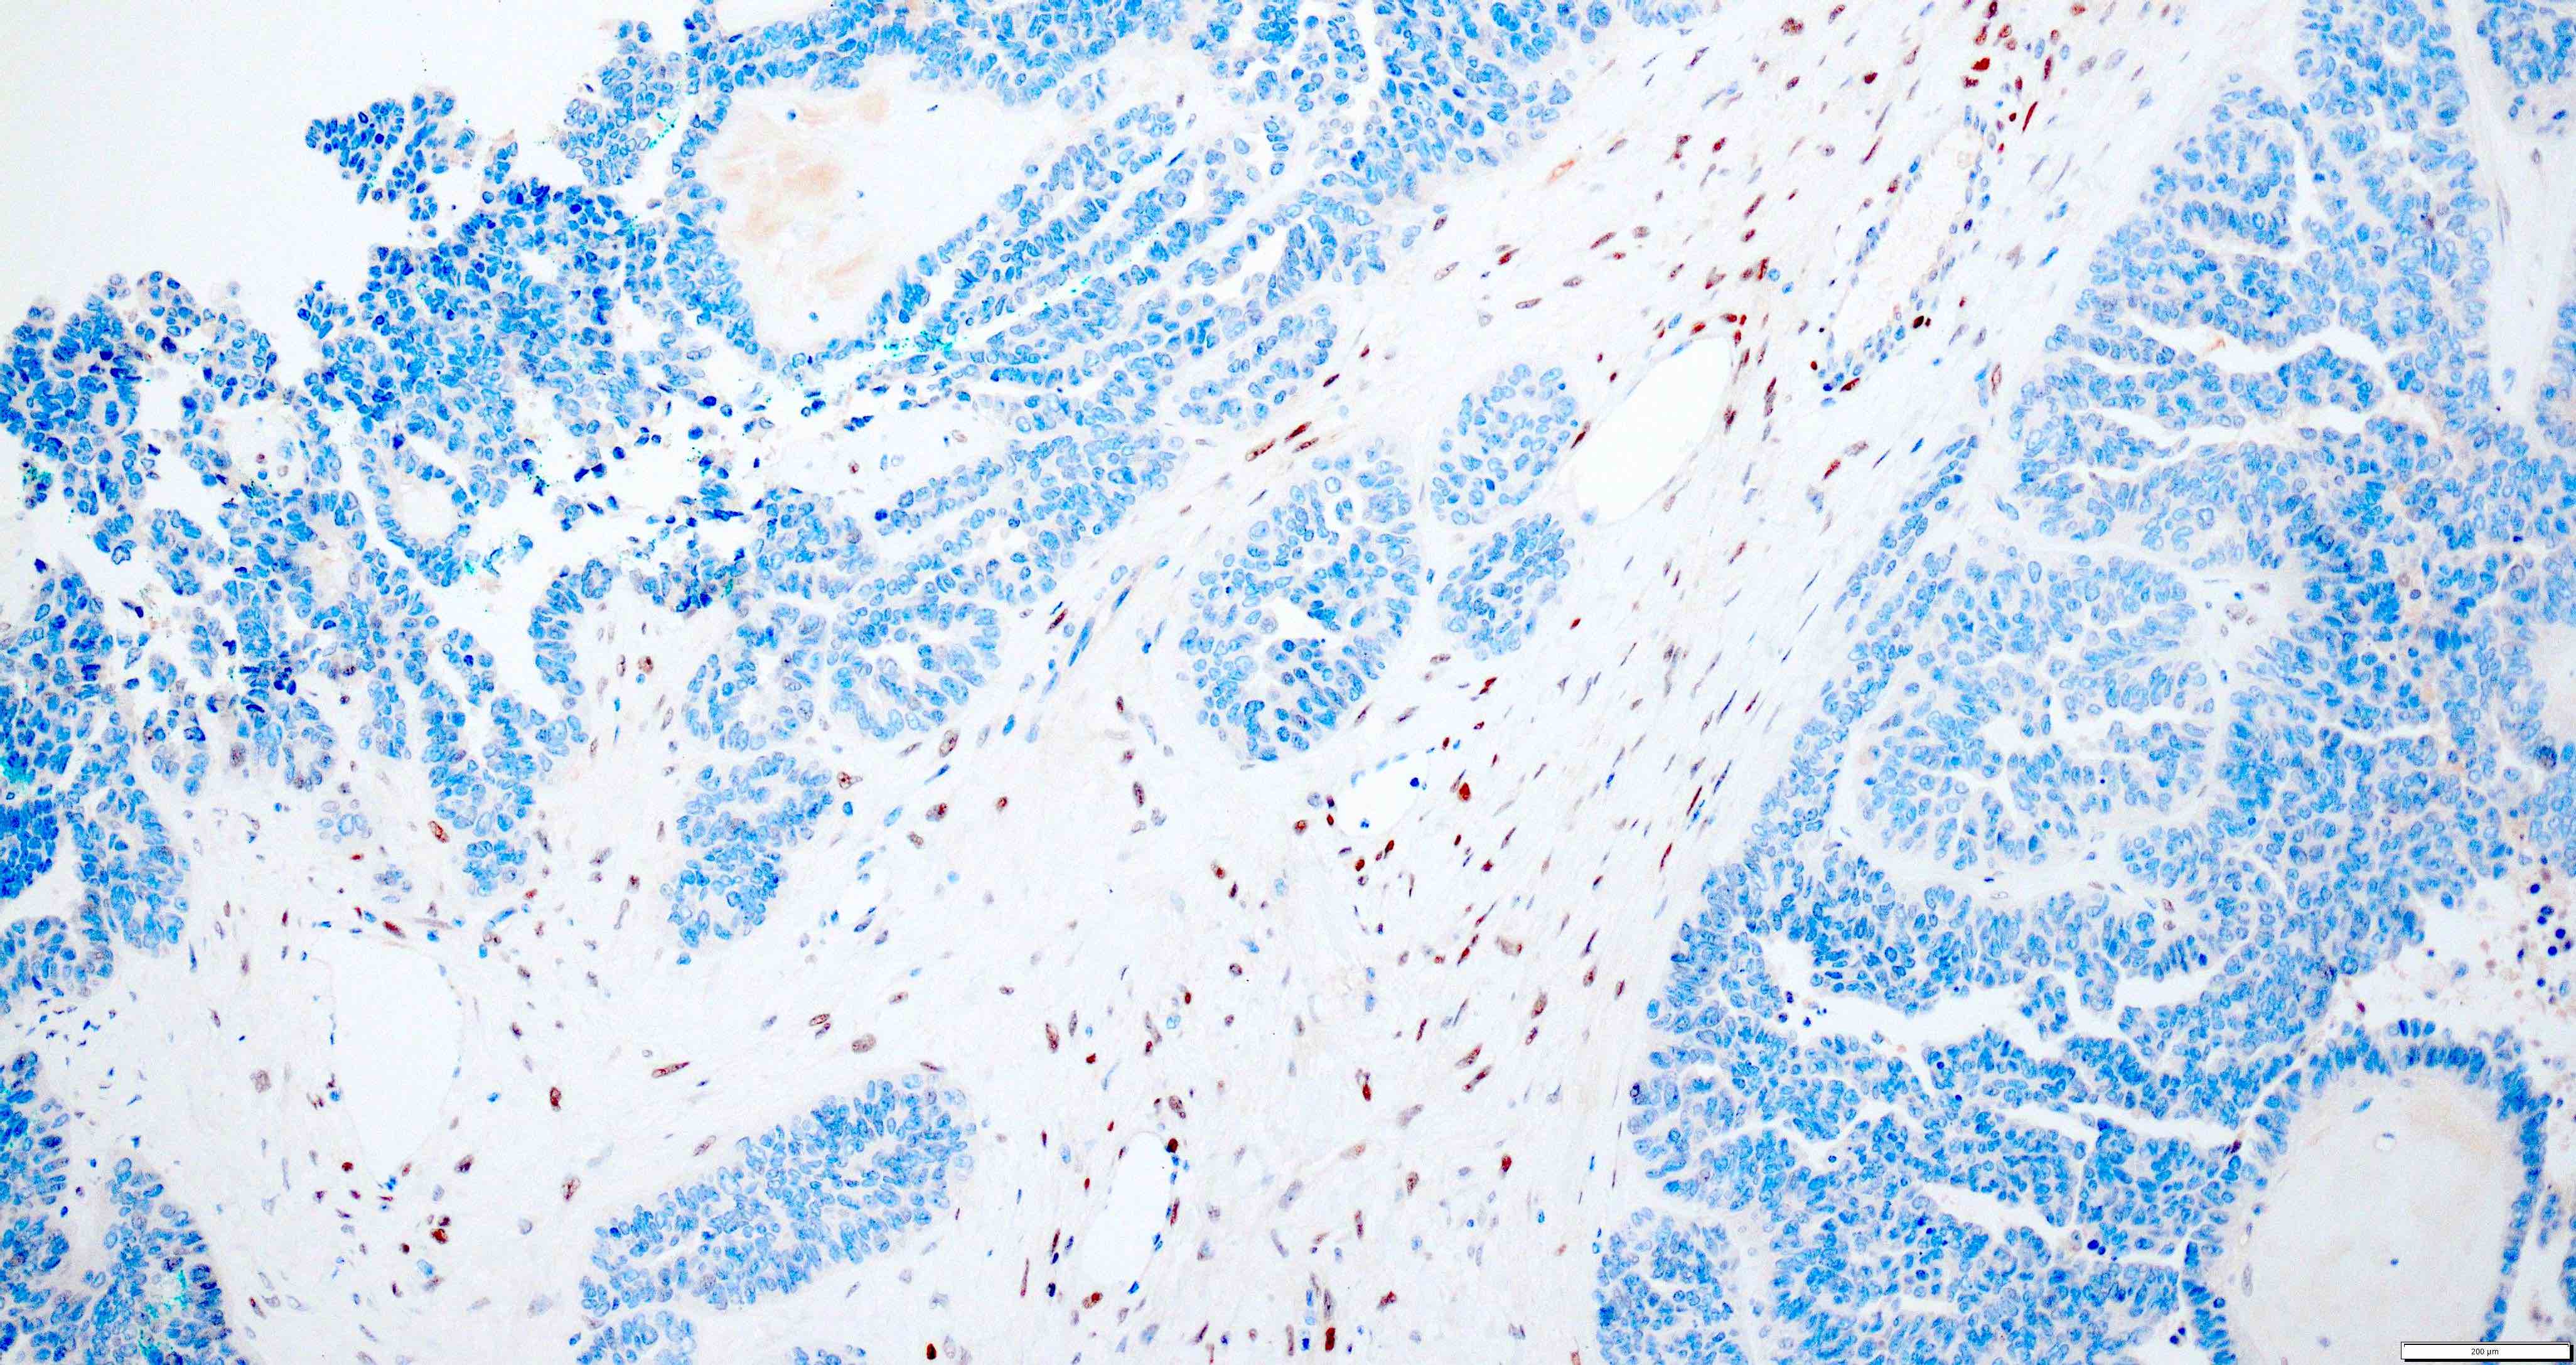

Microscopic (histologic) images

Contributed by Daniel Graham, M.D., Adele Wong, M.B., B.Ch., B.A.O. and Lucy Ma, M.D.

Positive stains

- PAX8: usually diffusely positive

- GATA3 and TTF1: focal or diffuse with inverse staining pattern described in several studies in the most recent WHO classification; cells positive for GATA3 are negative for TTF1 and vice versa (Am J Surg Pathol 2018;42:1596)

- CD10: focal and apical / luminal

- p53 wild type

- MMR proficient

Negative stains

- ER

- PR (more reliable negative marker than ER)

- Calretinin (usually negative may be focally positive)